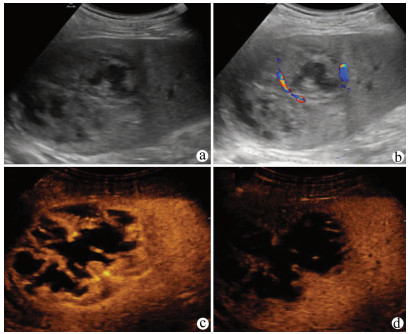

Guideline for ultrasonic diagnosis of liver diseases

Chinese Society of Ultrasound in Medicine, Oncology Intervention Committee of Chinese Research Hospital Society, National Health Commission Capacity Building and Continuing Education Expert Committee on Ultrasonic Diagnosis

2021, 37(8): 1770-1785. DOI: 10.3969/j.issn.1001-5256.2021.08.007

Abstract(3025) HTML (6526) PDF (9311KB)(794)

Abstract:

Ultrasound is a non-invasive, real-time, inexpensive, radiation-free and easily repeatable method, usually used for liver imaging. In recent years, new ultrasound examination techniques for liver diseases such as contrast-enhanced ultrasound and elastography have been rapidly developed, which can effectively identify intrahepatic space-occupying lesions, assess the degree of liver fibrosis and portal hypertension, and monitor the effects of treatment. Therefore, these technologies play an important diagnostic role in clinical liver diseases and have therapeutic interventional value. This guideline classifies the instrument set-up, patient preparation, and physician examination methods through multimodal ultrasound examinations (gray-scale ultrasound, color Doppler ultrasound, contrast-enhanced ultrasound, elastic ultrasound) for liver diseases. In addition, liver diseases multimodal ultrasound technology diagnostic criteria for diffuse hepatic lesions (inflammatory lesions, fibrosis, and sclerosis), multiple space-occupying lesions, and interventional procedures have been defined and standardized. Concurrently, we also recommend the ultrasound monitoring time interval and diagnostic report writing standard for liver diseases.